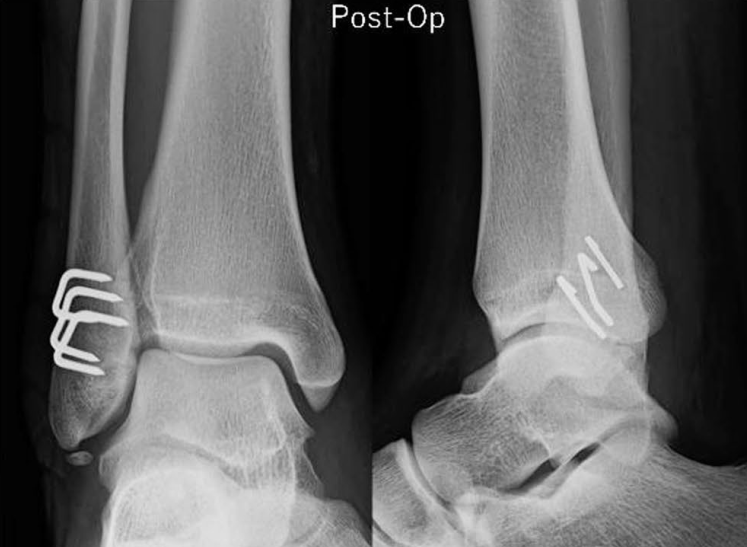

除临时固定外,单纯采用骑缝钉固定外踝骨折,也可避免钢板螺钉的内植物刺激,且在骨折愈合率上不存在劣势: